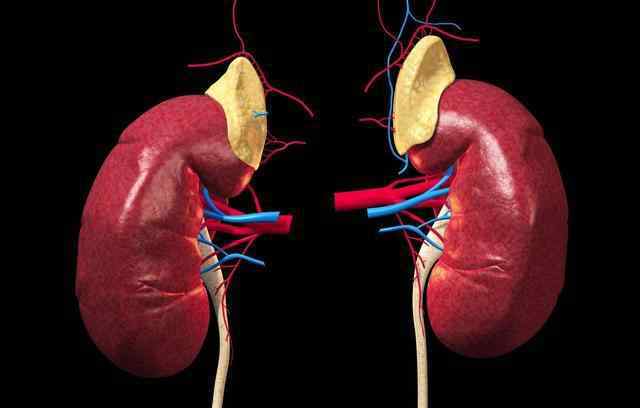

血清肌酐不仅是肾功能的重要指标,也是患者是否达到透析的重要指标,可以说是透析的“分水岭”指标。所以血清肌酐的变化也影响肾友的心。所以,如何降低血清肌酐?避免肌酐升高?这是每个人在治疗肾脏疾病时都特别注意的一点。

降低肌酐,最关键的只有一点,你是否已经认识到?血清肌酐的形成分为两部分,内源性肌酐主要是肌肉的代谢产物,外源性肌酐主要是吃肉后产生的。肌酐本身就是体内的一种垃圾。正常情况下,会被肾脏过滤后排出体外,达到平衡。但肾功能受损时,过滤能力下降,产生的肌酐不能及时排出体外,导致蓄积,血清肌酐的检测会增加。

所以要减少肌酐积累,除了减少肉类摄入,避免剧烈运动外,关键是恢复肾功能。

但我们都知道肾功能受损后是不可逆的,所以要避免肌酐升高,就要避免肾功能的恶化。主要要做到两点:一是控制蛋白尿、高血压等症状的发展,二是避免感染、肾毒性药物、饮食不当等加速肾功能急性进展的因素。